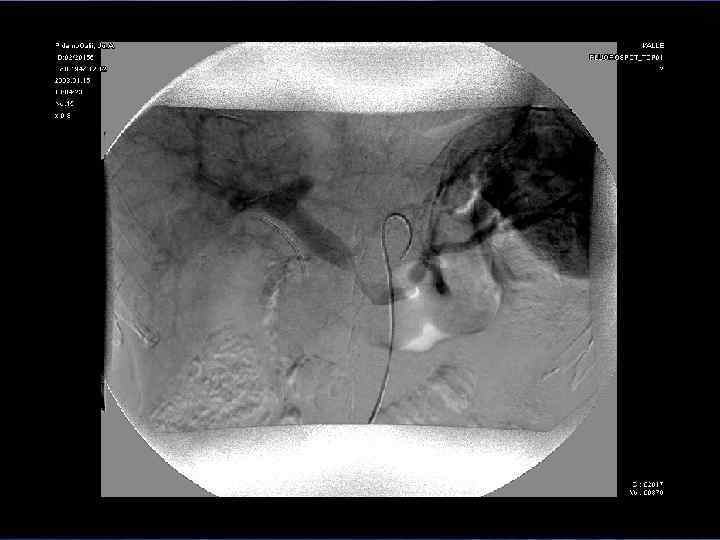

Чрескожная чреспеченочная холангиостомия (ЧЧХС) • Наружное дренирование • Наружно-внутреннее дренирование • Раздельное дренирование правой и левой долей печени • Дренировние протоков левой доли через правый долевой проток и опухолевую окклюзию

Чрескожная чреспеченочная холангиостомия (ЧЧХС) а а б б в в Схема чреспеченочного одинарного (а – наружного, б – наружновнутреннего) и двойного наружно-внутреннего (в) дренирования желчных протоков

Чрескожная чреспеченочная холангиостомия (ЧЧХС) Наружно- внутреннее рентгенэндобилиарное дренирование системы желчных протоков правой доли печени а а – схема, б б – общий вид налаженной системы.

Чрескожная чреспеченочная холангиостомия (ЧЧХС) Раздельное наружное рентгенэндобилиарное дренирование правого и левого долевых протоков печени а а – схема, б б – общий вид налаженной системы.